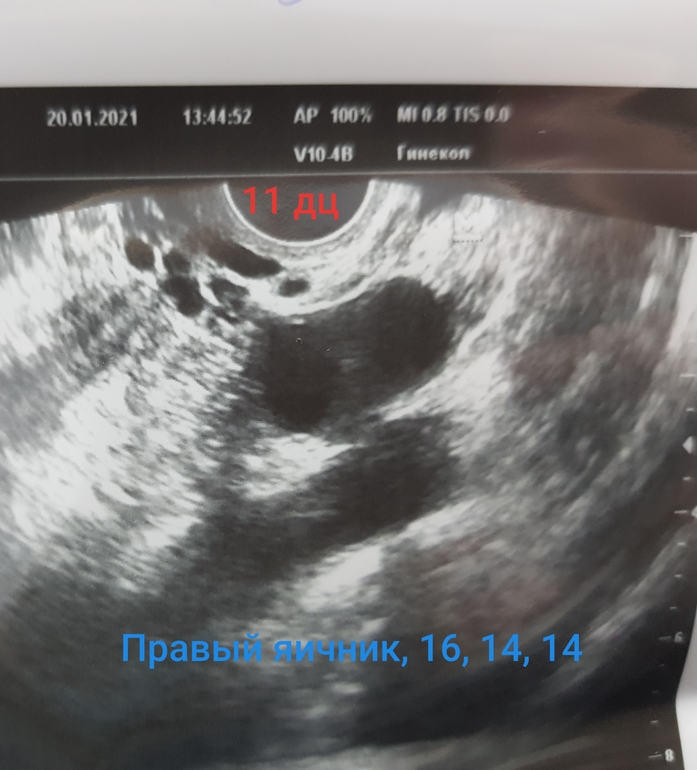

На стимуляции, была на узи (фото ниже) на 8й, 11й и 16й дц.

На 11й в ЛЯ 19мм, в ПЯ так и остались 16, 14, 14.